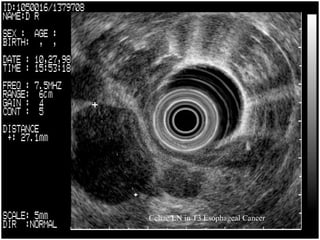

Celiac LN in T3 Esophageal Cancer

T3 Esophageal Cancer   Aorta   <invasion   <Muscularis Propria   LN   Azv